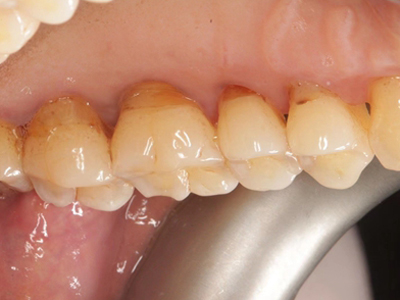

牙龈退缩牙根暴露出现黑斑图

牙龈退缩患者的上排多颗牙齿处的牙龈出现回缩,从而导致牙根外露,外露的牙根上存在黑色的牙菌斑、牙结石,伴有口臭、牙根面敏感等症状。